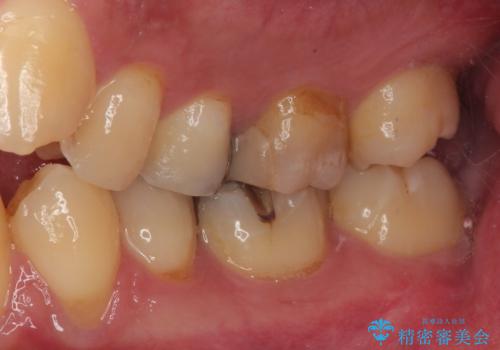

検査の結果、虫歯が非常に深く、通常であれば神経をすべて取り除く抜髄処置が必要な状態でした。

神経をすべて取り除いてしまうと歯の寿命が縮まってしまうため、感染している神経の一部を取り除く生活歯髄療法を行っていくことご提案しました。

生活歯髄療法を行い状態が安定していることを確認してからオールセラミッククラウンによる補綴治療を手前の銀歯を含め2本同時に行いました。